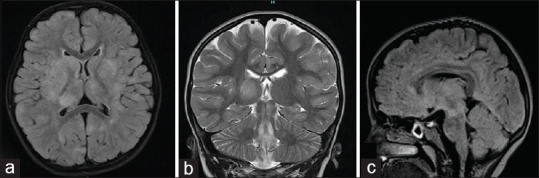

Results: 204 /416 children with suspected meningoencephalitis were included in the study. HHV 6 was detected in 12 children. The median age was 19 months (Range - 6 months to 16 years). 4 (33%) of them were classified as febrile status. 5 (42%) children had meningoencephalitis, and one had aseptic meningitis. One child each had features of probable acute demyelinating encephalo myelitis (ADEM) and anti NMDA receptor encephalitis. 9 (75%) children had uneventful clinical recovery, one child died, one child with probable ADEM had extrapyramidal signs at discharge, which improved completely at one year follow up and the baby with autoimmune encephalitis had significant neurological deficits.